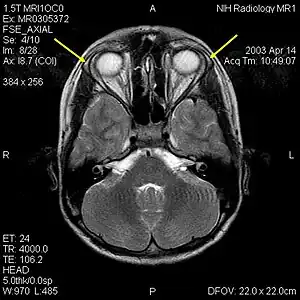

MRI of the brain of 12-year-old boy with triple-A syndrome showing hypoplastic lacrimal glands (yellow arrows.)